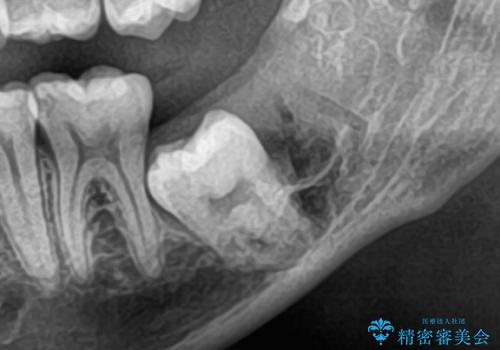

- 当院で矯正治療予定の患者さんです。下顎水平埋伏智歯による下顎第二大臼歯の歯周病やう蝕のリスクを考慮し抜歯をする事になりました。

今回の下顎水平埋伏智歯は歯茎と骨に埋まっていたので、麻酔をした後に歯茎を切開し骨を削って抜歯をしています。抜歯後、糸を縫って1週間後に抜糸に来ていただいています。抜歯後1週間は痛みとお顔の腫れがあり、度合いには個人差があります。